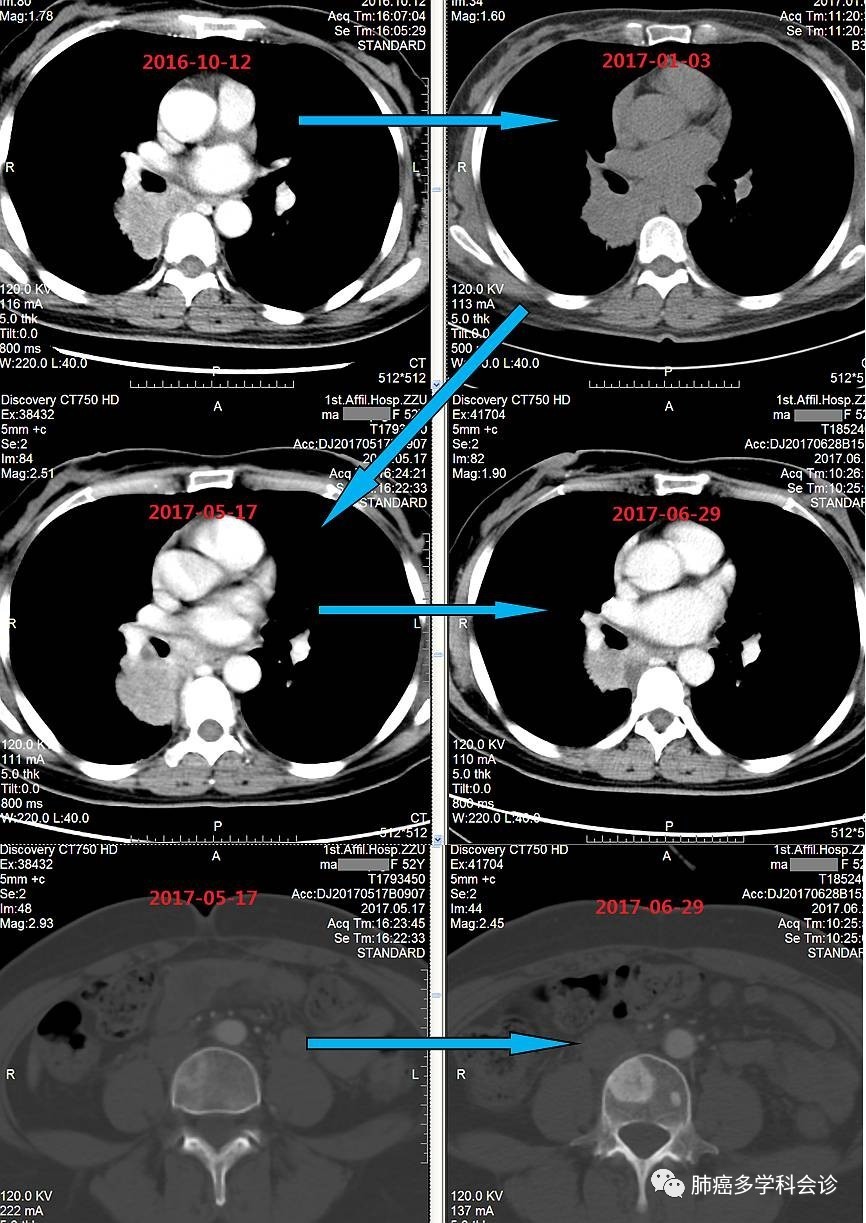

患者马ZQ,女,51岁,2016 年 9 月因大咯血做胸部CT发现右肺占位,拒绝活检,盲服“吉非替尼“,45天后自行停药,未再治疗。

2017-01-03 复查 CT发现病灶稍增大,气管镜活检病理诊断为:腺癌

患者拒绝治疗,院外口服中药治疗。

2017.05 复查 CT:右肺病灶较前稍增大,腰 2、4 椎体内高密度影,右肺中下叶多发小结节。“培美曲塞 + 顺铂”化疗 2 周期后病灶都有不同程度减小,腰4椎体病变范围较前显著(成骨加强是治疗有效的标志之一)。目前完成 3个周期化疗,升高的血清肿瘤标志物 CEA 和 CA125 均明显下降。

疗效评价:部分缓解(PR)。

微信图片_20170717104655.jpg以下为患者疾病进程中复查CT肺部病灶变化情况: